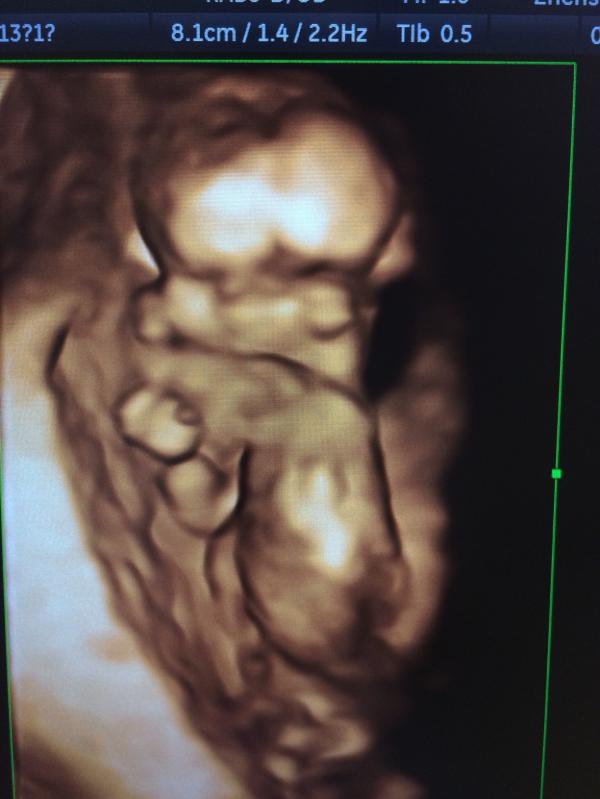

39 неделя 🤰🏽живот опустился, голова уже низко, плацента II степени зрелости, вес 2650г 🤗 началось какое-то затишье, тренировочные даже прекратились 🤷🏽♀️ очень уж хочется родить 31 октября или 1 ноября, как это сделать? 🙈 долгие пешие прогулки, мужатерапия, половина бокала вина, уборка-и все равно тихо как в танке 😔